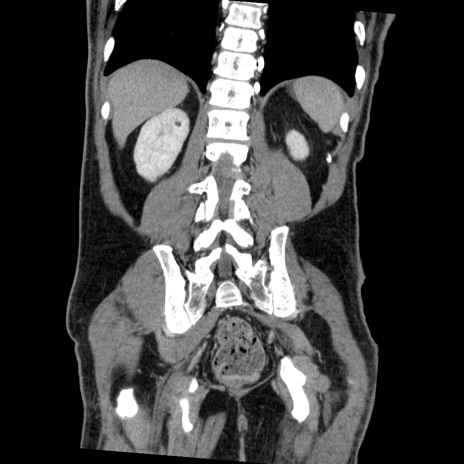

症例22(冠状断像)

【症例】50歳代男性

【主訴】腹痛

【現病歴】AVMからの被殻出血のため回復期リハ病棟入院中。 本日午後3時頃急に下腹部痛が出現した。

【既往歴】AVM、被殻出血、虫垂炎、高血圧

【身体所見】意識晴明、左半身不全麻痺、会話の理解は良好、36.5°C、腹部:膨隆、全体に板状硬、下腹部正中に圧痛点あり、反跳痛-、筋性防御不明、右下腹部にope scar

【データ】WBC 9400、CRP 0.06